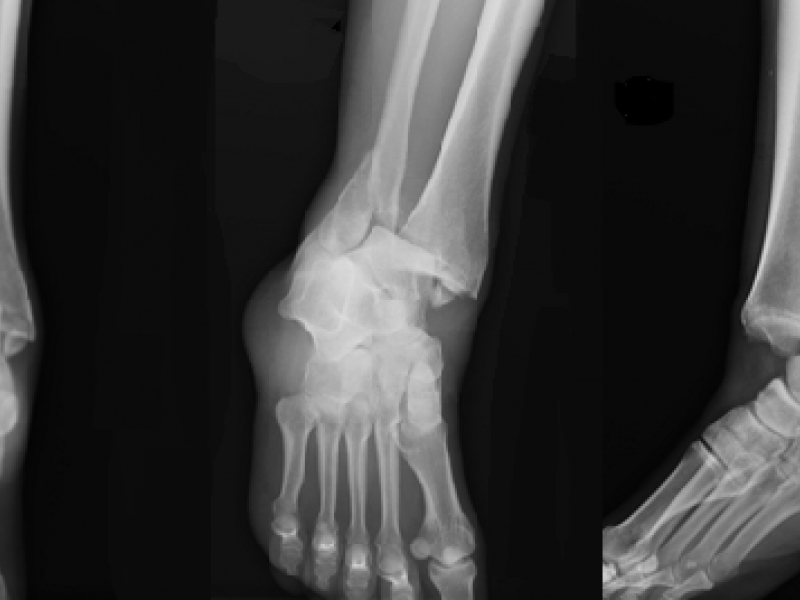

What's the Diagnosis? By Dr. Danielle Kovalsky

A 41 yo F presents to the ED with R ankle pain after a fall